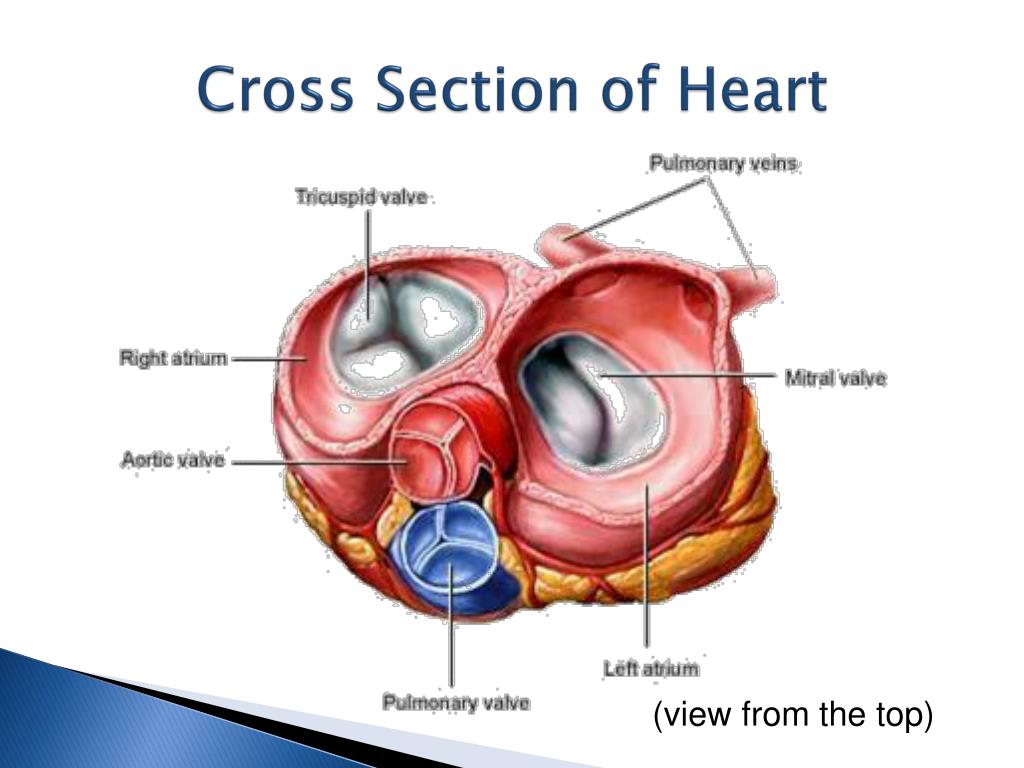

Фотографии и информация о приобретенных пороках сердца